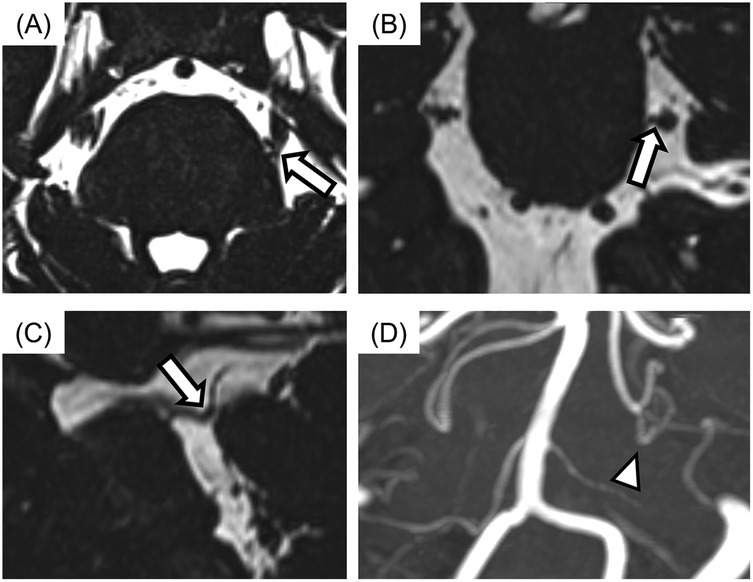

All MR images were obtained at the REZ of the trigeminal nerve by using a three-tesla MRI scanner (Magnetom Spectra, Siemens, Germany) with a 16-channel head coil according to our previous study (15, 26). MR angiography (MRA) was obtained using 3D time-of-flight (3D-TOF) MRA with the following parameters: repetition time/echo time, flip angle = 24/3.9 ms, 18°; field of view 160 mm × 160 mm; matrix 320 × 192; section thickness 0.5 mm; and slab number 3. MR cisternography was obtained using 3D-constructive interference in steady-state (3D-CISS) MRA with the following parameters: repetition time/echo time, flip angle = 7.4/3.7 ms, 50°; field of view 160 mm × 160 mm; matrix 320 × 320. These MR images were reconstructed to a voxel size of 0.5 mm × 0.5 mm × 0.5 mm and slab thickness of 44 mm. All 3D-TOF and 3D-CISS images were displayed in triplanar views (transverse, coronal, and sagittal views) on the visualization system. Images were assessed for NVC presence by two experienced radiology specialists blinded to the laterality of symptoms. NVC presence was defined as contact between the blood vessel and the trigeminal nerve at REZ. When cerebrospinal fluid was not present between them in the 3D-CISS, it was defined as “with NVC” (Figure 2). In case of disagreements or uncertainties, whether there was contact or not, it is regarded as “without NVC”. Regarding details of NVC, the blood vessels involved in NVC and the degree of NVC, whether with only simple contact or with compression or displacement, were assessed (Figure 3).

Figure 2

Four MRI and MRA images labeled A, B, C, and D show different cross-sectional views of brain structures. Panel A highlights a region with a thick arrow. Panel B shows a similar highlighted area. Panel C has an arrow indicating the same area from another angle. Panel D is an MRA showing blood vessels, with a triangle marker pointing to a particular vessel region.

Figure 2. The images of neurovascular compression (NVC) with the trigeminal nerve. (A) Axial view, (B) sagittal view, (C) coronal view, (D) display of 3D time-of-flight magnetic resonance angiography (3D-TOF MRA). The case with no cerebrospinal fluid between the trigeminal nerve and blood vessel was assessed for NVC presence (arrows). Responsible blood vessel: the superior cerebellar artery (arrowhead) was revealed by using 3D-TOF MRA.